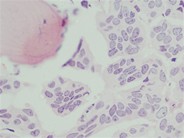

A 36-year old man presented with abdominal tenderness and pain in both legs. He had no significant medical history and was using acetaminophen and opioids for his pain. A CT-scan showed no abnormalities except for diffuse sclerosis of the lumbar spine and pelvic bones,  which could fit the diagnosis of myelofibrosis, metabolic disorder or malignancy (A). A bone marrow biopsy showed 100% cellularity (B). Using the Gomori trichrome staining, grade 2 fibrosis was demonstrated. However, there was no splenomegaly and the abdominal pain was not understood. A PET-CT scan showed metabolically active mediastinal and hilar lymph nodes. A histological biopsy showed CK7-positive epithelial cells with the typical morphology of signet ring cells (C). Subsequently a gastroscopy confirmed the diagnosis of gastric cancer. With this finding, an additional staining on the bone marrow biopsy also showed solitary signet ring cells (D). He was thus diagnosed with gastric cancer with lymph node and bone marrow metastases. Previously, secondary myelofibrosis had been described as a rare paraneoplastic syndrome. The clinical course was complicated by cerebral, kidney and spleen infarctions. His (neurological) condition deteriorated, possible due to new cerebrovascular events which occurred despite anticoagulant therapy, and unfortunately he passed away one month after presentation.